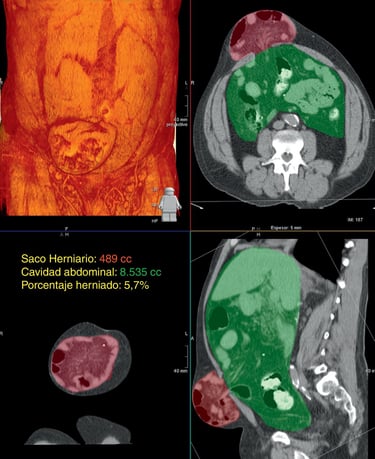

Realizamos una Tomografía Axial Computarizada con reconstrucción en 3D de la Pared Abdominal y de la hernia, cuando corroboramos que todo está listo, el siguiente paso es elegir el tipo de malla quirúrgica a colocar en la cirugía.